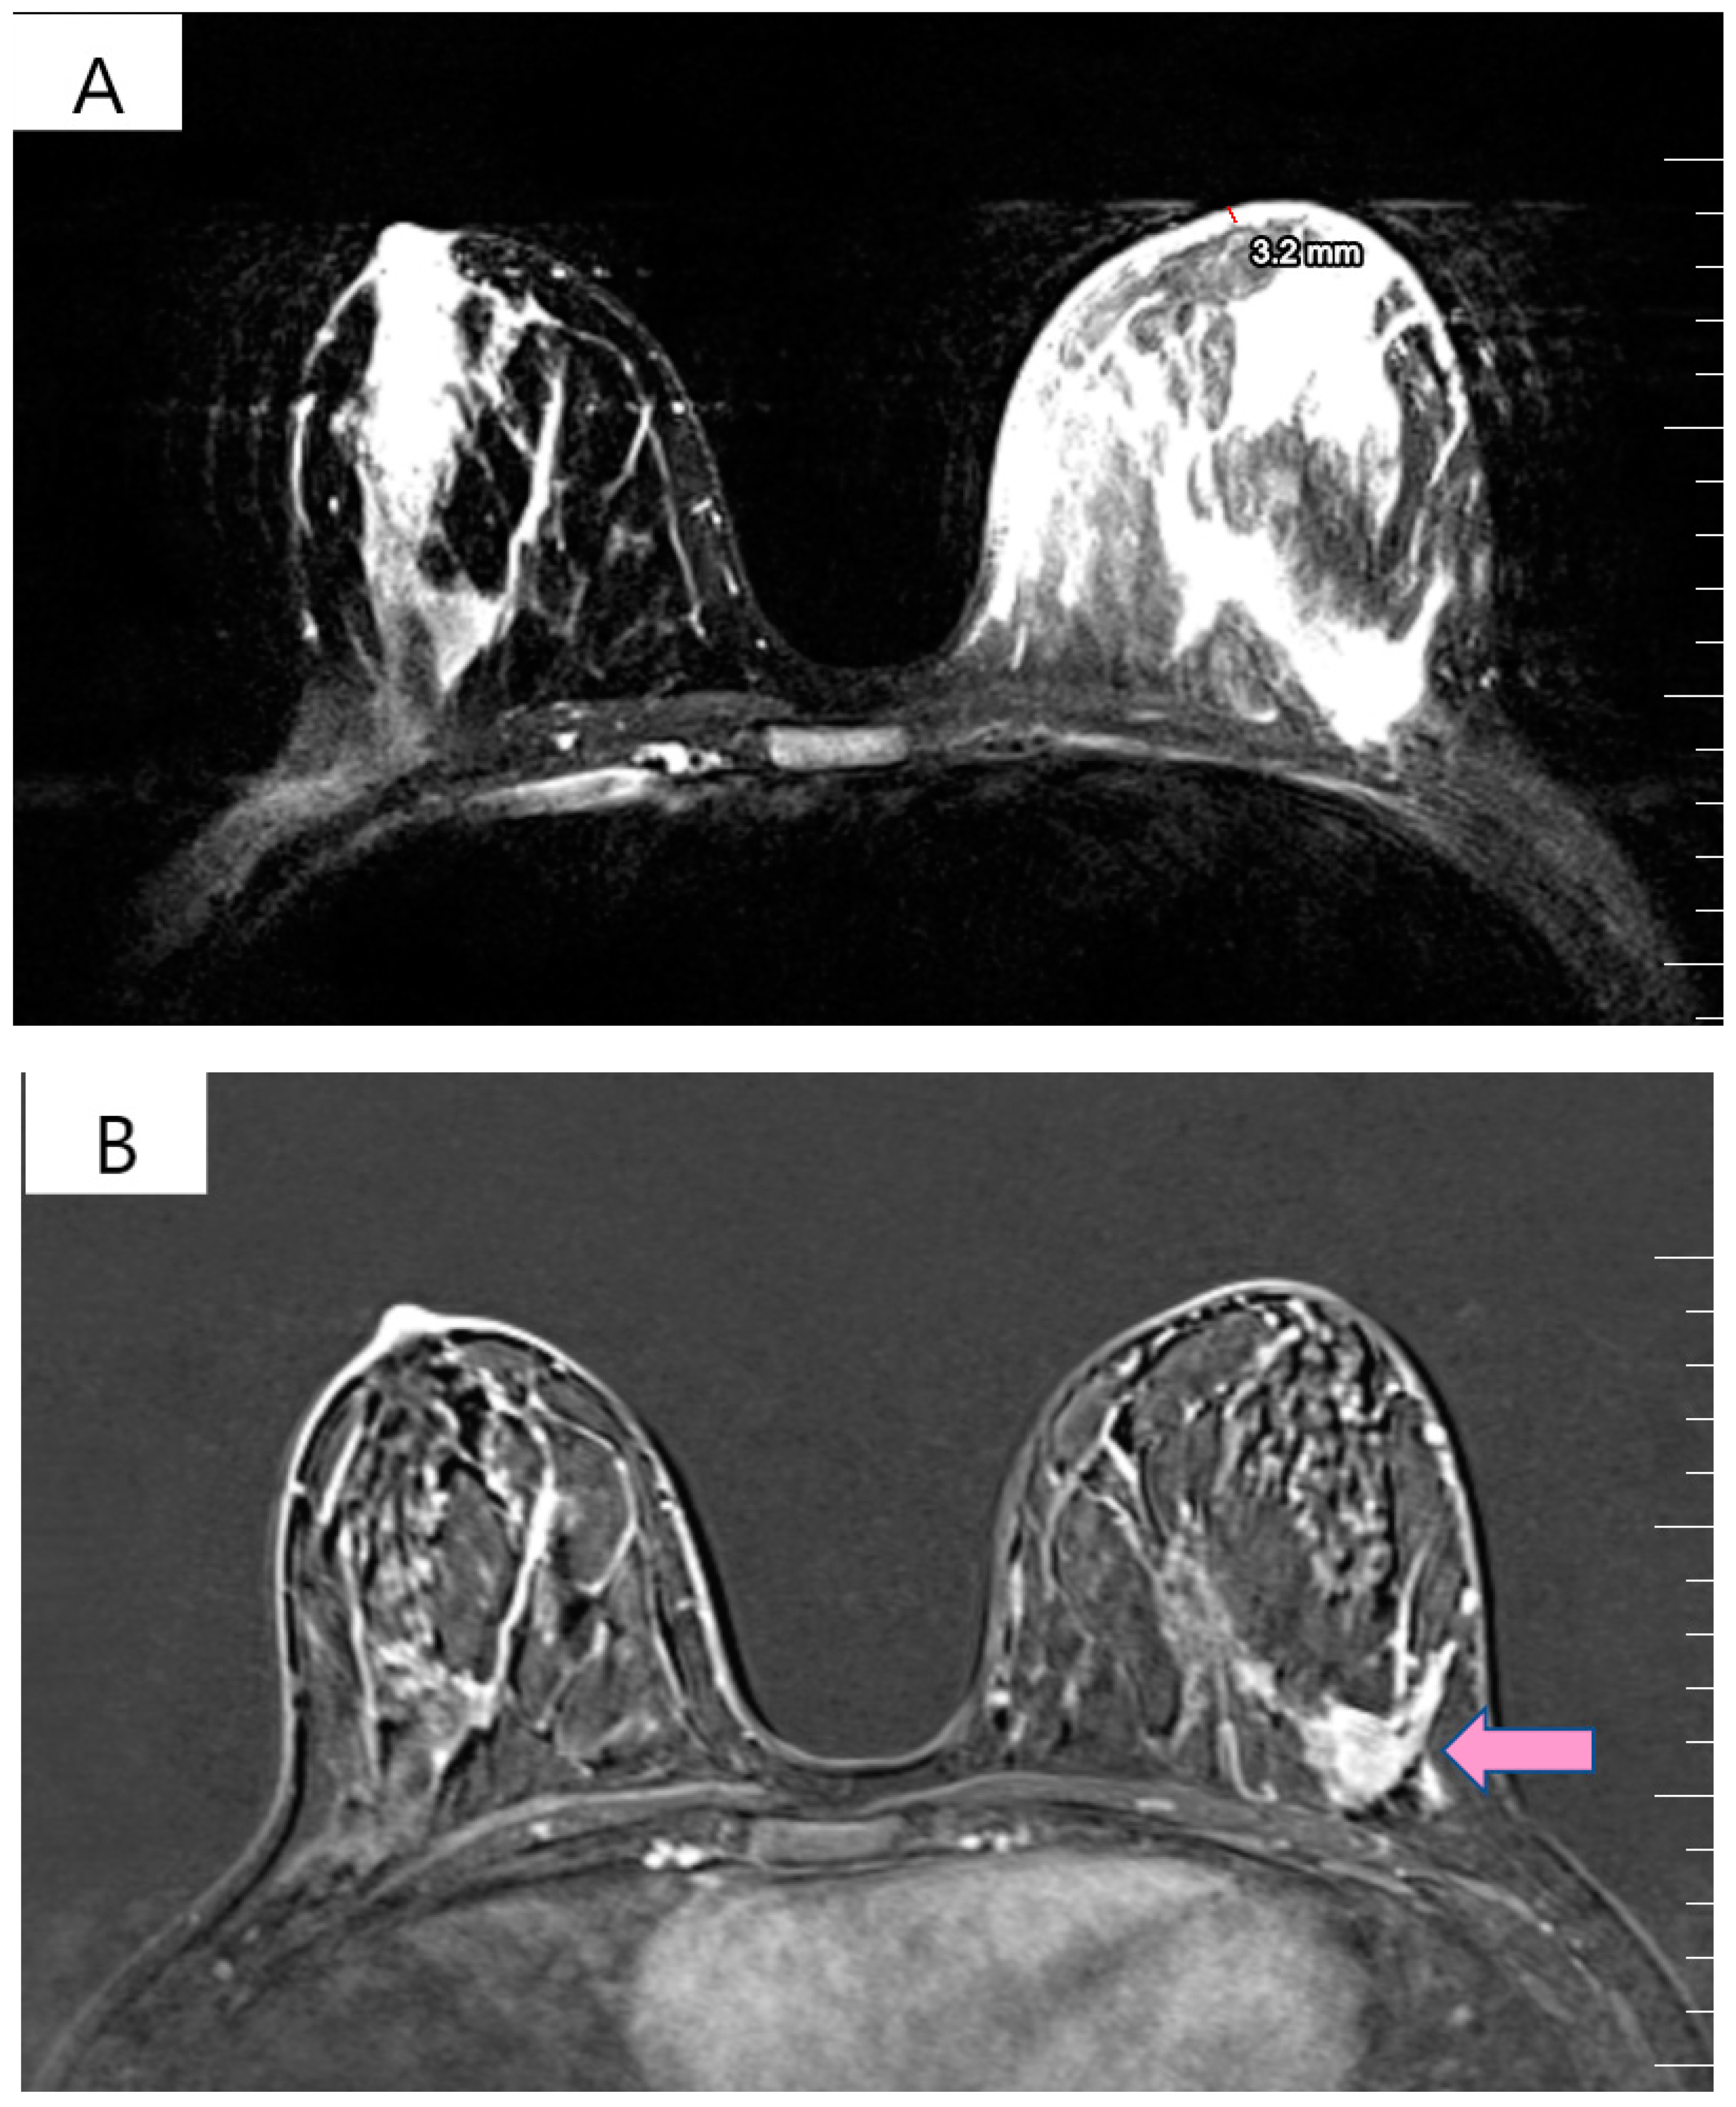

The physical exam revealed a tumor in the outer quadrants of her left breast measuring 3/2.5 cm which was associated with erythema, skin thickening, purulent mammary secretions and a mobile ipsilateral axillary adenopathy. Magnetic resonance imaging (MRI) revealed a lower outer quadrant tumor with extensions to the upper outer quadrant (Figure 1A,B). The biopsy and the following pathology exam of this ill-defined mass showed an invasive mammary carcinoma of no special type, moderately differentiated (grade 2 of 3) with solid areas of in situ carcinoma of mixed differentiation and extensive comedonecrosis (Figure 2). Further immunohistochemistry showed that the tumor expressed estrogen receptor (ER 70%), progesterone receptor (PR 20%), HER2 overexpression and a Ki-67 index of 40% (luminal subtype, HER2+). An ulterior whole-body computed tomography (CT) highlighted a suspicious 44/40/52 mm tumor in the caudate lobe of the liver and no other metastases. For a better description of the lesion, an MRI was ordered which described it as a focal hyperplasic nodule (HFN). Lab reports and tumor-marker carbohydrate antigen 15-3 were within normal values (CA15-3 = 18.8 U/mL). Correlated with these findings, the tumor was staged as T4bN1M0 stage IIIB according to the AJCC cancer-staging manual (eighth edition).

Figure 1.

(A) T2 weighted MRI of left breast demonstrating skin thickening (3.2 mm) associated with hypersignal suggestive of edema. (B) T1 weighted MRI showing the regional contrast sample located in the lower outer quadrant extending to the upper outer quadrant (marked by arrows).